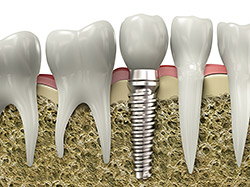

An implant is a synthetic tooth root in the shape of a post that is surgically placed into the jawbone. The implant “root” is usually made of titanium: the same material used in many replacement hips and knees, and a metal that is well-suited to integrating with human bone. After the implant is placed and integrated into the jaw bone, it can be restored with a crown to replace a missing tooth.

Dental implants are different than traditional dental prosthetics in the sense that they replace the entirety of the missing tooth (root and crown) without affecting adjacent teeth. A conventional bridge requires the cutting down of healthy tooth structure of the teeth adjacent to the missing teeth. If one of the teeth supporting the bridge goes bad, the entire bridge will need to be replaced

The advantage of replacing the root with a dental implant is that the bone in that area stays healthy and is not lost. Also, the instability of conventional bridges and dentures can make it difficult to eat or smile with confidence. Implants look more natural, have a stronger biting force, and feel like natural teeth.